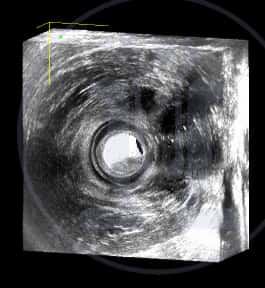

Ασθενής γυναίκα με φλεγμονή στο πεπτικό, προσέρχεται με αδυναμία στην συγκράτηση των κοπράνων. Στο ιστορικό της αναφέρει εγχείρηση με την μέθοδο του Ιπποκράτη. Ανευρίσκονται μετεγχειρητικές αλλοιώσεις του έξω σφιγκτήρα.